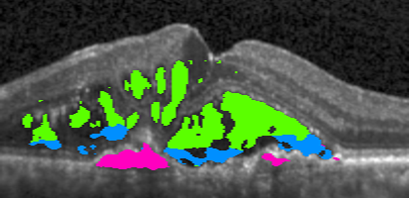

Input 666 121212 242424 Full Access Target

Refer to caption Refer to caption Refer to caption Refer to caption Refer to caption Refer to caption

Baseline

Our approach – Multi-label Deep Supervision

MIL Baseline

Deeply Supervised MIL

Our approach – Mean-Taught Deep Supervision

Figure 4: Segmentation progression when increasing the number of pixel-wise annotated masks from 666 to 121212, 242424, and full access. The upper two methods leverage only pixel-wise masks while the remaining three methods have access to weak annotations (image-level labels).

4.6 Qualitative results

In \figreffig:qualitative, we show segmentation results as more annotations are added for the Baseline and Multi-label Deep Supervision models as well as some semi-weakly supervised results. Comparing the first two rows, we observe the advantageous effect of our deep supervision technique, especially in the low-data setting. Similarly, when comparing our deep supervision in Mean-Taught models (bottom row) to the rest, we directly see in column two and three that our models nicely segment the fluid regions, even with extremely few samples while other methods fail severely.